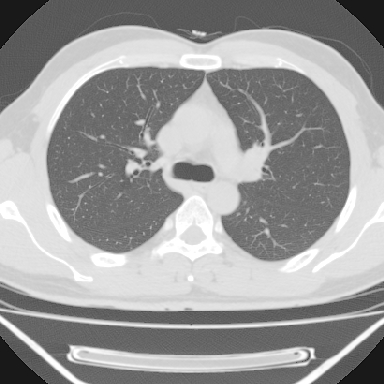

m 30 右胸痛10年

右上后纵隔旁软组织肿块影,与肺界面光滑,与胸壁呈钝角相交,提示肺外病变。位于肋骨下缘,边缘清楚,呈三角样指向与右侧椎间孔,但并示进入椎间孔;与对侧神经根对比,属同一走行方向。

考虑后纵膈良性肿瘤,神经源性肿瘤可能大。

鉴别:胸膜来源肿瘤。影像表现虽有肺外征象,但无胸水等相应佐证;再者,病史前10年,超长,与胸膜肿瘤不太吻合。

右上后纵隔脊柱旁见长椭圆形肿块,边界光整,与胸壁呈钝角。周围骨质未见异常。

考虑、1、后纵隔神经源性肿瘤;

2、不除外单发胸膜间皮瘤。

右上后纵隔脊柱旁类圆形肿块,边界光整,与胸膜呈钝角,首先考虑来源于肺外,神经源性肿瘤(神经纤维瘤可能大)。